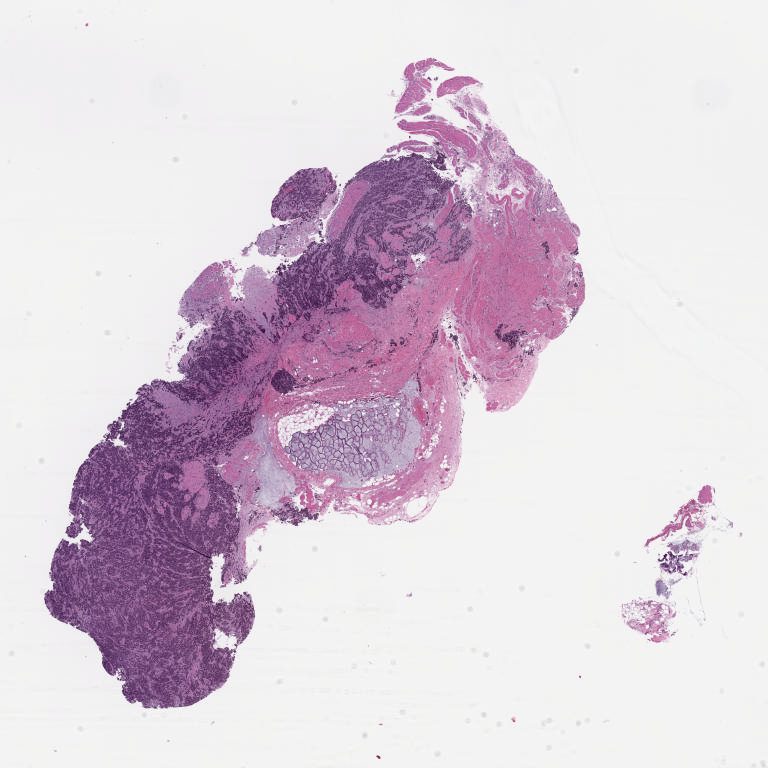

964751.svs

967118.svs

967127.svs